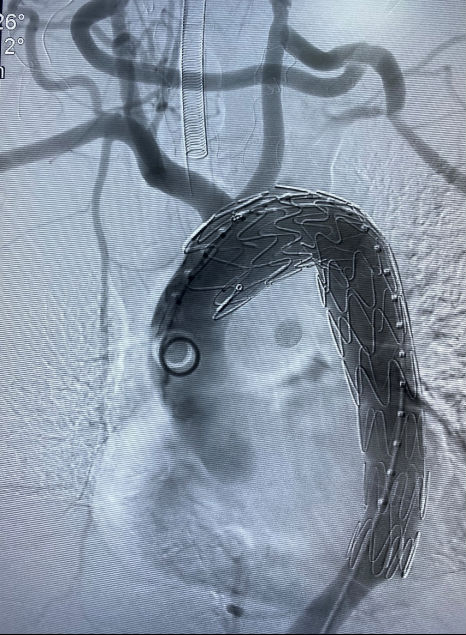

3月17日15时左右 ,在手术麻醉中心的配合下,心胸外科专家何东权副院长带领心胸血管外科张文林主任、王贤芝主治医师、薛春竹主治医师、何杨医师在复合手术室急诊行主动脉弓部血管去分支+人工血管吻合+左肾动脉球囊扩张、支架植入+胸主动脉支架植入术(IV型杂交)。

历经8小时浴血奋战,手术顺利完成,患者转入重症监护室进一步监护治疗。

图3.术后造影显示:右无名动脉-右颈总动脉-人工血管-左颈总动脉-人工血管-左锁骨下动脉血管通畅,主动脉支架安稳在位,无内漏。